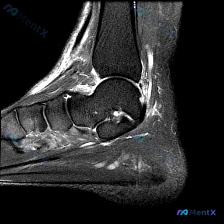

整理了一个最近看到的很有意思的病例资料,最关键的是那个容易被忽略的背景信息。 病例核心影像与事实 - 研究对象:双胞胎 Twin A 与 Twin B(提供的分析重点在 Twin A) - 检查部位:踝关节 + 骶髂关节 MRI - 关键影像(Twin A 左踝矢状位 T2WI): 1. 跟腱止点处...